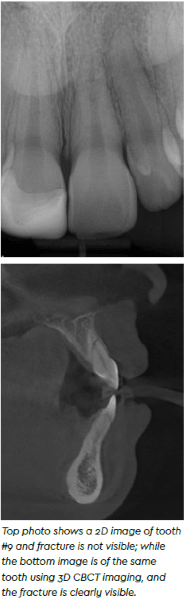

The new system has been especially useful for endo procedures. “If you’re considering the first molar on the maxillary arch, many times that will have a second canal in one of the root systems, and that canal is hard to see,” she explained. “The Axeos allows for better clarity of the canal, so that when you’re actually doing the procedure, you know you’re not going to miss it,” she continued. Dr. Andrews also incorporates another software to create a guide that allows her to drill to that exact spot, which is especially useful when a tooth is highly calcified and the canal isn’t visible until the most apical portion.